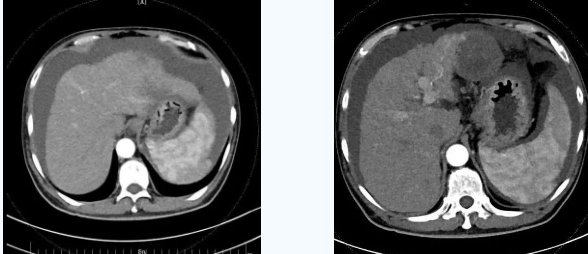

術(shù)后一個(gè)月秦先生來(lái)院復(fù)查,腹水已明顯較前減少,精神和飲食較術(shù)前明顯好轉(zhuǎn)。

韓國(guó)宏院長(zhǎng)介紹,TIPS原理是采用特殊的介入治療器械,在X線透視導(dǎo)引下,經(jīng)頸靜脈入路,建立肝內(nèi)的位于肝靜脈及門(mén)靜脈主要分支之間的人工分流通道,并以金屬覆膜內(nèi)支架維持其永久性通暢,達(dá)到降低門(mén)脈高壓后減少腹水產(chǎn)生,控制和預(yù)防食道胃底靜脈曲張破裂出血的目的。